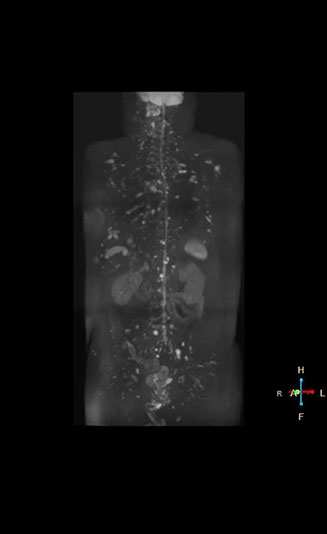

Radiologist Hiroshi Nobusawa, MD, PhD, explains that the coronal DWIBS protocol for whole body DWI is excellent for visualizing lesions in oncology patients. “About 90% of the DWIBS exams are done in this type of patients. The remainder of DWIBS exams are performed to gain information in cases of fevers of unknown origin,” he says.

“The DWIBS sequence’s value in oncology cases is due to the high contrast it creates between lesions and surrounding tissue. Whole body DWI is requested by physicians who need to clarify TNM staging or determine therapeutic strategies, oncologists in need of diagnosis or follow-up scans, surgeons who need to see the presence of distant lesions that are sometimes difficult to detect by CT before surgery, and urologists for the evaluation of bone lesions, and the effect of chemotherapy and radiotherapy.”

High contrast between lesions and background is beneficial in oncology patients